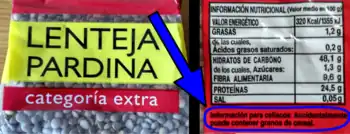

El cumplimiento de la dieta en los celíacos es mucho peor de lo que tradicionalmente se consideraba por parte de los científicos y especialistas.[77] Estudios actuales demuestran que aproximadamente el 80 % de los celíacos continúa teniendo lesión intestinal, a pesar del tratamiento mantenido con la dieta sin gluten.[78] La principal causa de esta falta de recuperación es la ingesta inadvertida de gluten, principalmente debida a contaminaciones cruzadas.[12][79] Un meta-análisis de 2018 concluye que la mayoría de los celiacos, especialmente los adultos, pero también los niños, sigue ingiriendo gluten con regularidad, de manera involuntaria, a pesar de estar haciendo una dieta sin gluten.[80] Con frecuencia, las personas con una educación básica pobre y una baja comprensión de cómo se realiza una dieta sin gluten creen que están siguiendo estrictamente la dieta, pero están cometiendo errores frecuentes.[12][13] Un problema habitual es la poca conciencia del paciente para evitar las contaminaciones por gluten en la preparación de sus alimentos y otras fuentes comunes de gluten,[81] como la avena, las hostias de comunión, las bebidas malteadas, los medicamentos, los alimentos procesados, las comidas en restaurantes y eventos sociales.[81][82][83] Comer fuera supone un gran riesgo puesto que a pesar de ofrecer un menú "libre de gluten", muchos establecimientos (restaurantes, comedores escolares, etc.) no siguen estrictamente las normas para evitar la contaminación cruzada.[11][84] El gluten también puede afectar por inhalación.[85] A fecha de 2018, salvo en Brasil,[86] no es obligatorio en ningún país del mundo etiquetar los productos como "Sin Gluten" ni tampoco declarar la presencia de trazas de gluten, por lo que la simple lectura del listado de ingredientes no permite saber si un producto es seguro.[77][87][88] Si la supresión del gluten no es completa y mantenida de por vida, persisten el daño en la mucosa intestinal, la activación inmunitaria y el riesgo de desarrollar complicaciones de salud muy graves.[28]

La DSG debe ser estricta, eliminando de la alimentación todos los productos que contengan o se cocinen con harina de trigo, centeno, cebada y avena (dieta TACC), que son los cuatro cereales con gluten, y sustituyéndolos por harina de maíz y arroz sin trazas de gluten, evitando contaminaciones inadvertidas y todo tipo de transgresiones dietéticas.